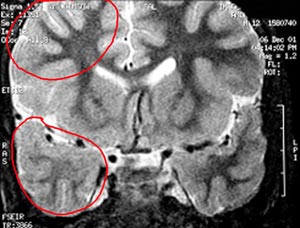

5b) Displasia cortical têmporo-occipital (lobos temporal e occipital)

Figura 69 - Ressonância nuclear magnética pré-operatória.